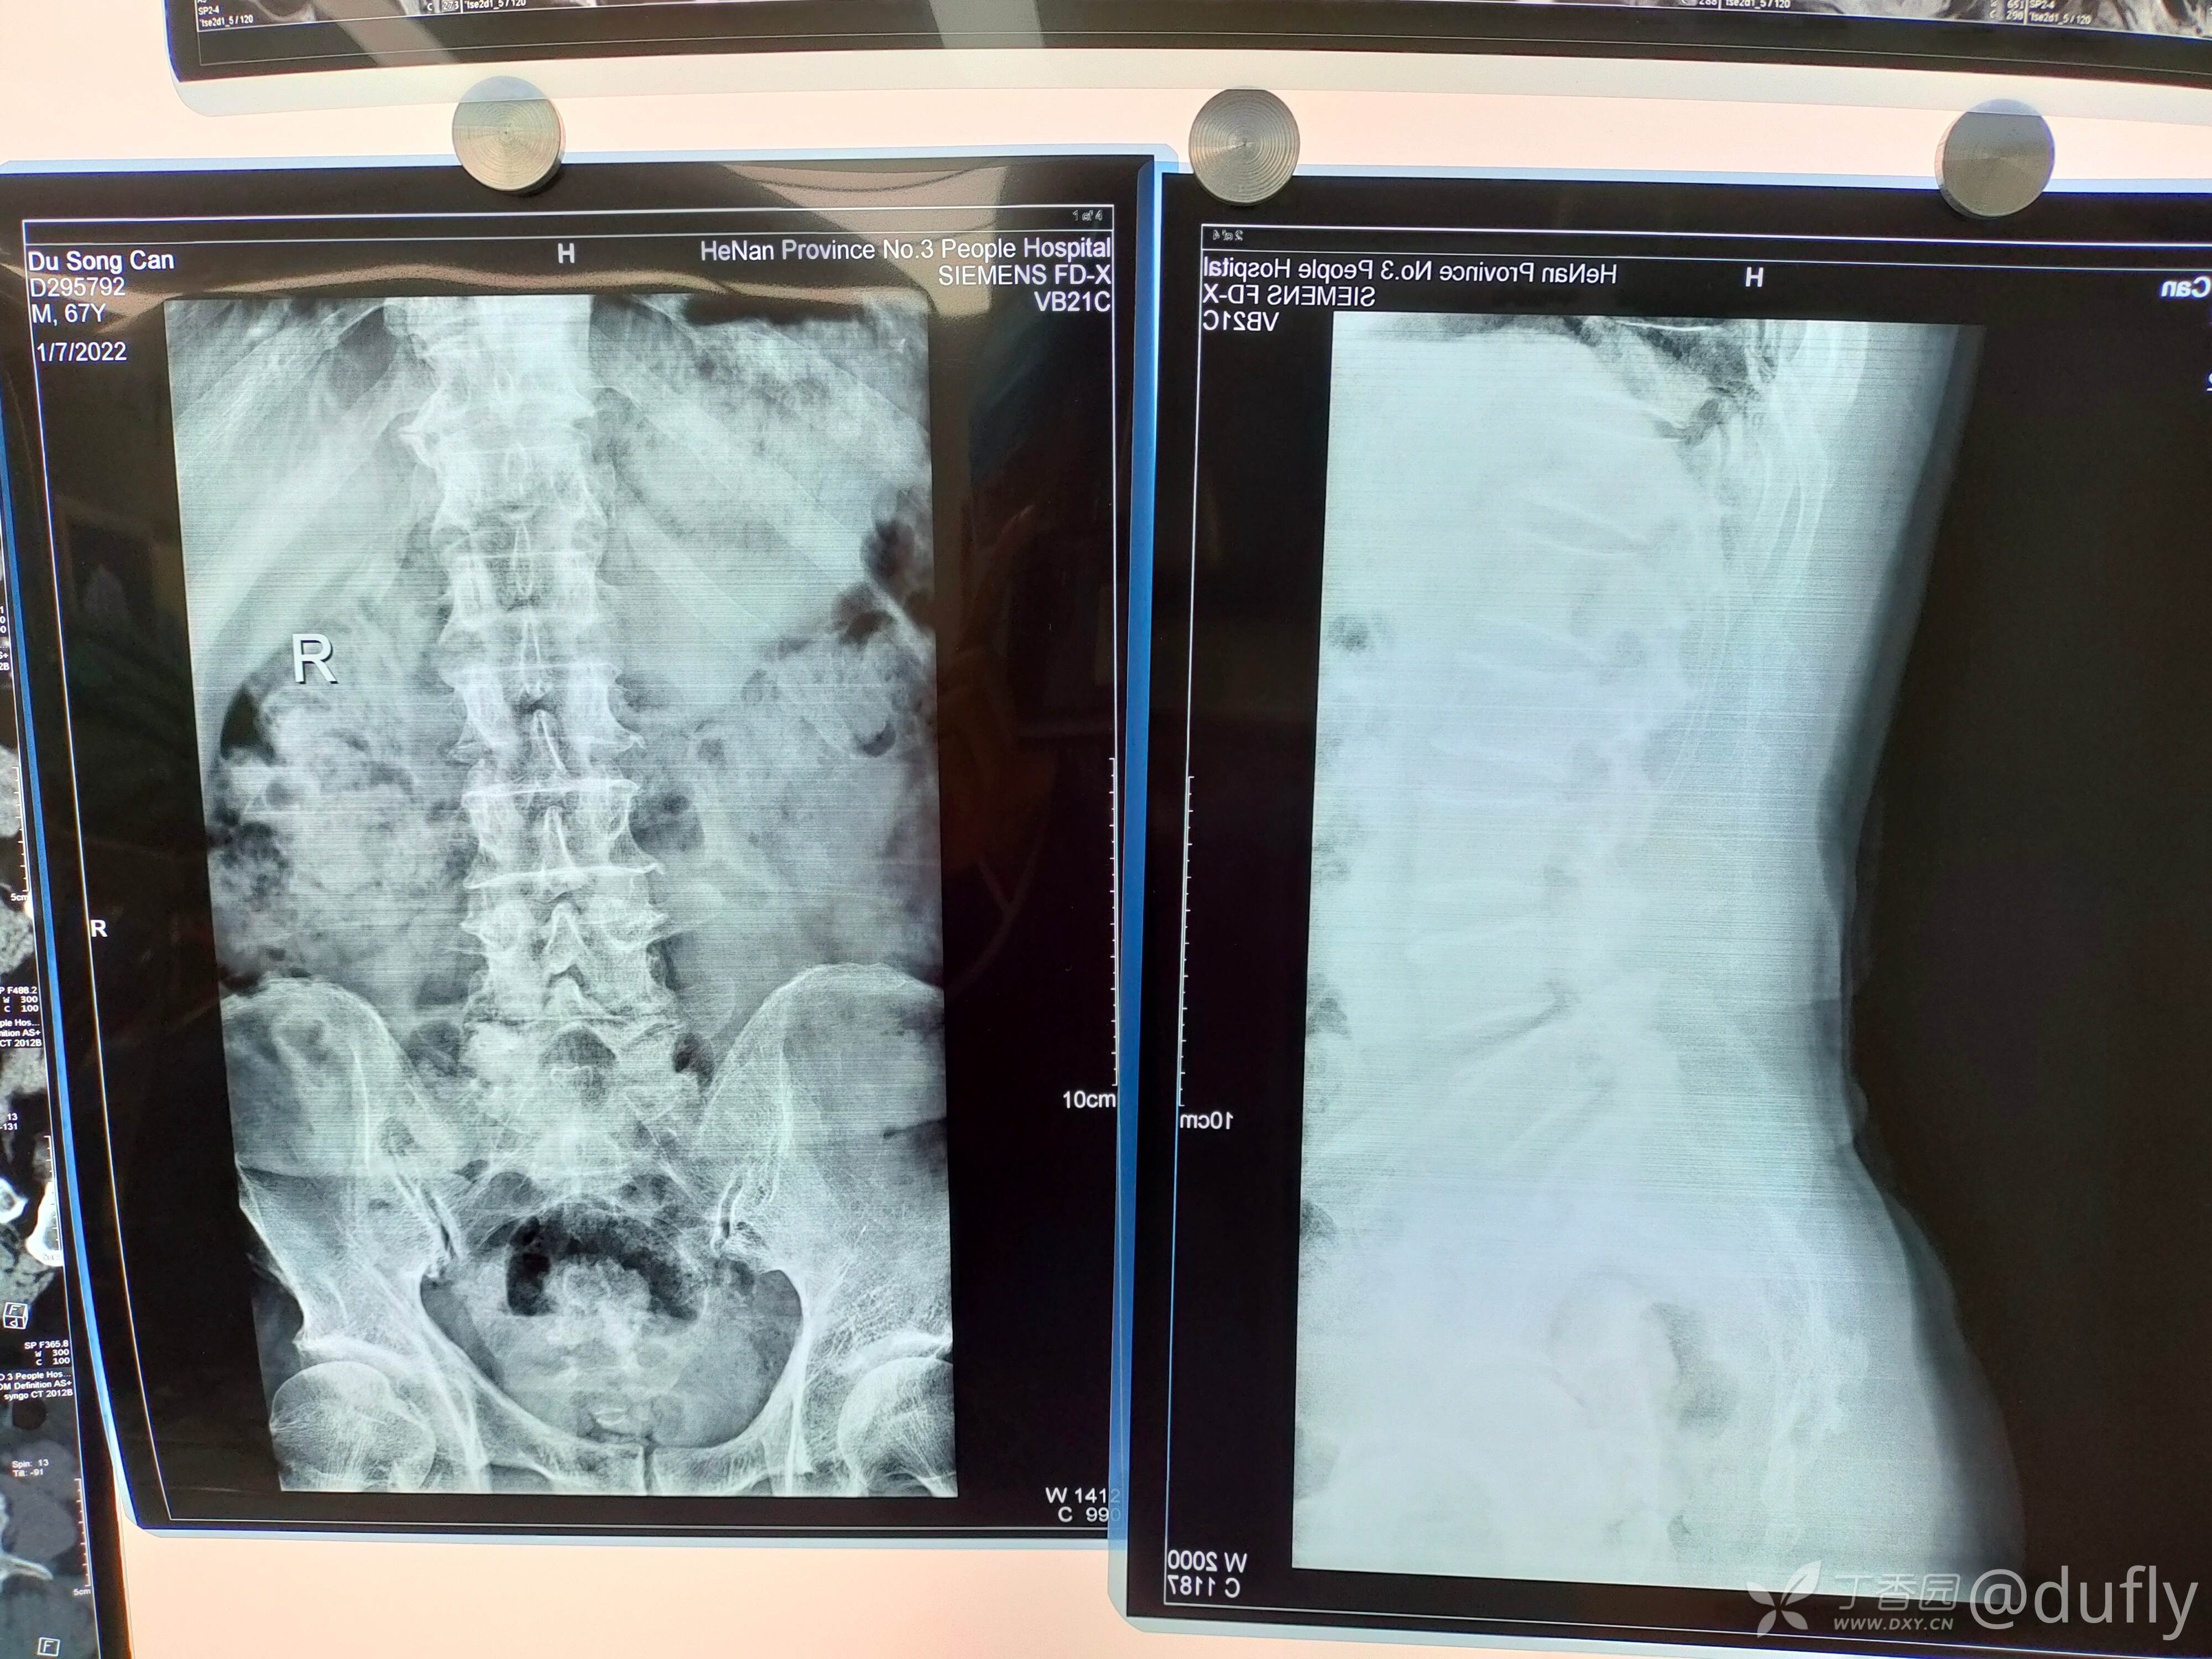

这是一个将近70岁的男性,半年之前间歇性跛行,大概350米。保守治疗后有所缓解。近一周下肢放射性疼痛加重,几乎不能行走。

腰椎核磁:腰45重度椎管狭窄。腰5骶1左侧极外侧突出。

初步诊断:腰椎管狭窄症(L4/5),腰椎间盘突出症(L5/S1,左侧,极外侧)。